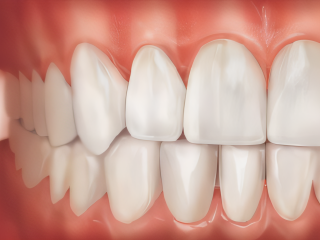

Parodontologie

Est-ce que vous saviez qu’on peut soigner avec succès les maladies de la gencive ?

Prendre soin de vos gencives, les fondations de votre sourire. La santé de vos dents dépend de la santé de vos gencives et de l’os qui les soutient.

Les maladies gingivales et parodontales touchent plus de 50% de la population adulte et sont dans la grande majorité des cas une manifestation d’une infection de bactéries et de parasites buccaux.

Nous traitons les inflammations et les maladies parodontales (déchaussement) pour stabiliser vos dents et protéger votre santé globale contre les bactéries buccales.

Des études médicales récentes suggèrent un lien étroit entre la santé parodontale et la santé générale : les infections de la gencive pourraient avoir un impact sur le diabète, l’ostéoporose, les naissances prématurées de bébés de petit poids, les AVC, les maladies cardio-vasculaires et les infections respiratoires.